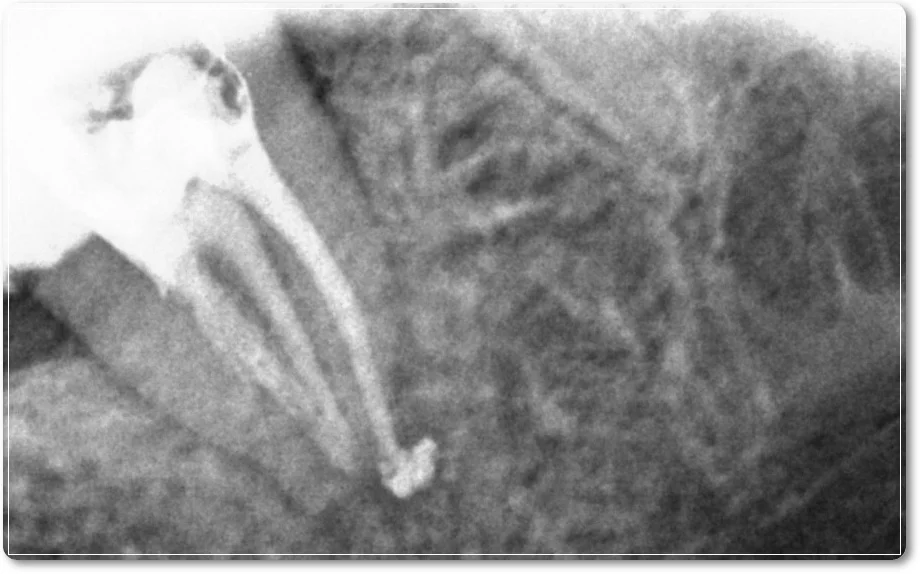

신경치료 과정에서 뿌리를 막고 있던 재료를 모두 제거하는 것 역시 쉽지 않은 작업입니다. 다행히 치아 뿌리 쪽 염증 부위까지 접근할 수 있었고, 방사선 촬영을 통해 해당 부분을 확인할 수 있었습니다.

신경치료는 성공적으로 마무리되었습니다.